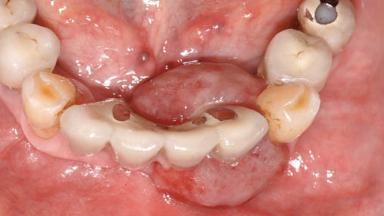

Peripheral Giant-cell Granuloma Associated with Peri-implant Tissues

| # of Teeth | 10 |

| # of Implants | 5 |